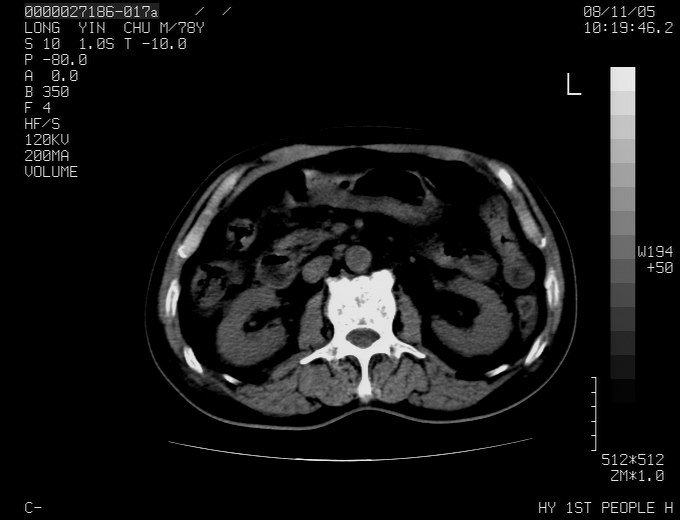

标题: CT16532:M78Y,肝脏病变,请会诊 [打印本页]

标题: CT16532:M78Y,肝脏病变,请会诊

腹胀,腹痛就诊,男性,78岁,外院b超未见异常。

肝ca,脾肾转移

支持脾肾转移瘤,双侧胸腔积液。

考虑弥漫性肝癌并脾及双肾转移.双侧胸水.

图片质量欠佳:多考虑:左侧肾癌。脾脏转移!胸膜转移!

肝脾肾转移瘤可能性大,左肾不除外梗塞,双侧胸水

考虑弥漫性肝癌并脾及双肾转移,双侧胸水。

考虑肝癌并双肾及脾脏转移;双侧胸腔积液。